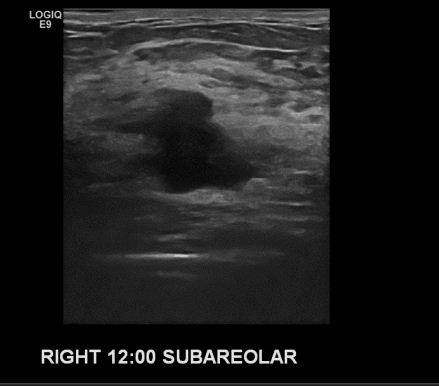

건강검진상 이상 소견으로 내원하신 40대 여성 분으로 우측 12시 방향 유두밑 으심

스러운 혹 조직검사 시행하여 침윤성 유방암 진단 되었습니다.